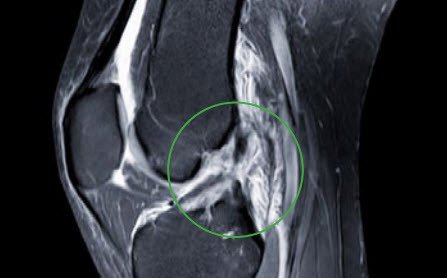

Der Arzt befragt den Patienten zu den aktuellen Beschwerden und dem Unfallmechanismus. Danach folgt eine gründliche klinische Untersuchung des Kniegelenks, wobei der Vergleich mit der gesunden Gegenseite wichtig ist. Weiterer Teil der Untersuchung ist die Röntgenabklärung des Kniegelenks, um eine Begleitverletzung des Knochens auszuschliessen. Meist sichert ein MRI die Diagnose und schliesst wichtige Begleitverletzungen (Seitenbänder, Knorpel, Menisken) aus (Abb. 2). Bei ausgeprägter Kniegelenkschwellung ist gelegentlich eine schmerzlindernde Entlastungspunktion des Kniegelenks notwendig.